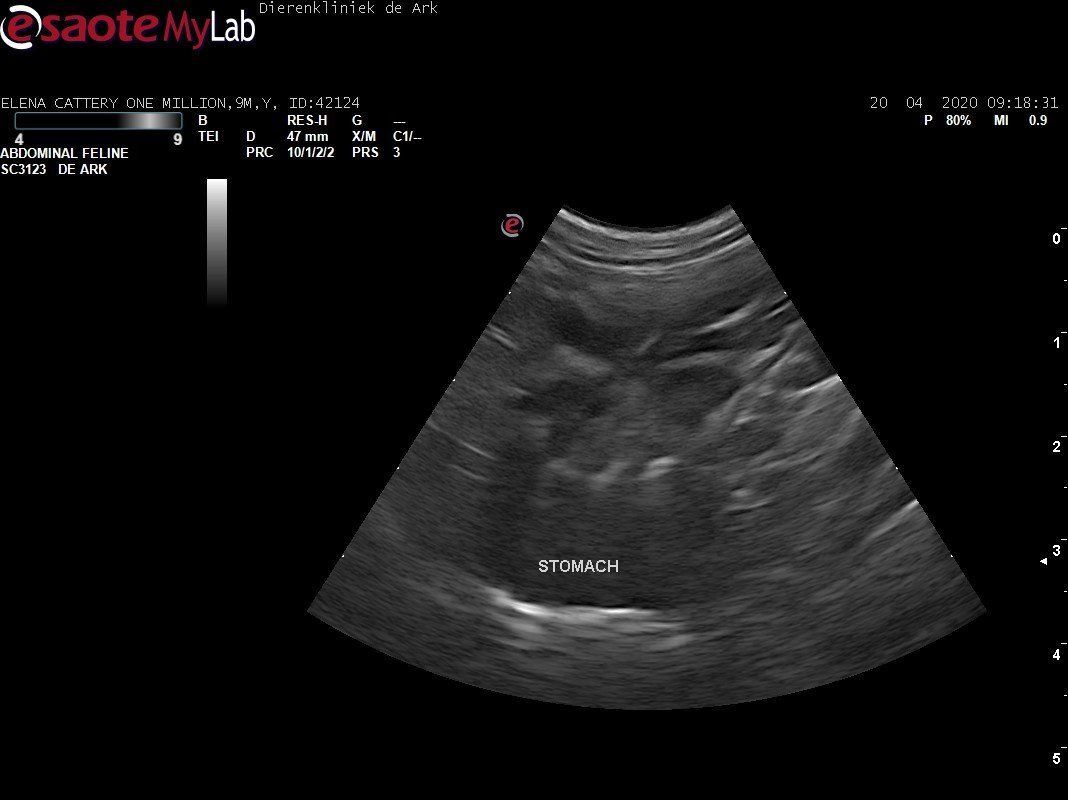

3,200 kg , echo en nieuw bloedonderzoek gedaan wat perfect ging door middel van gapabetine

Voor de garanties en om recht te hebben op medicatie bij herval eist Mutian diverse onderzoeken en controle momenten. Dit zijn bloedonderzoeken maar ook zoals hieronder te zien is echo's. Elana is volledig gecontroleerd op afwijkingen, gelukkig waren de echo's goed.

Ook de bloeduitslagen waren in orde, we kregen groen licht om te stoppen met behandelen en de wachtperiode in te gaan.